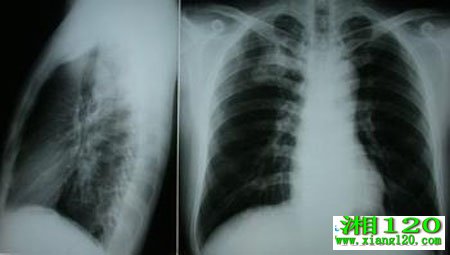

肺癌的常见危害由于痰阻或咯血凝块阻塞气管、支气管导致窒息。但不仅如此,肺癌还会转移,若肺癌转移至脑,引起颅内高压综合征,严重时会危及生命。若肺癌转移至脊椎,引起脊髓受压,会导致肢体感觉和运动障碍,甚至截瘫、大小便失禁等。若肺癌转移至心包,可能会引起心悸、气短、血压降低甚至休克。

1、咳嗽,如果您经常刺激性干咳,无痰或少量白黏痰,需提高警惕(尤其对于40岁以上长期重度吸烟者);2、咯血,多为血丝痰或痰中带血;3、轻度胸闷,如累及壁层胸膜或直接侵犯胸壁时,可以引起该部位持续性疼痛。

需要强调的是肺癌早期无特异症状,凡是超过2周治疗不愈的呼吸道症状或原有症状加重,都要警惕是否有肺癌存在的可能。